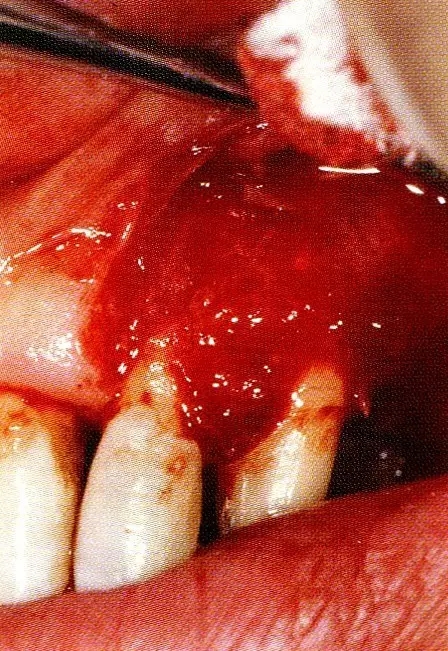

▲圖8-3  進(jìn)行全厚瓣翻瓣,將根表面的沉積物、骨缺損的肉芽組織徹底清除,確認(rèn)牙槽骨形態(tài),可看到從頰側(cè)到遠(yuǎn)中存在垂直性和水平性的骨缺損。